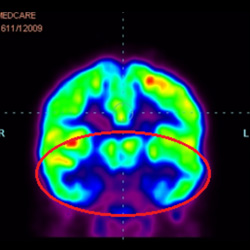

細胞治療后,藍色和黑色區域減少,并且看到更活躍的區域。這表明損傷減少并改善了大腦功能。

細胞治療前 PET CT 掃描顯示神經組織中的藍/黑色區域,表明腦癱引起的大腦損傷。

這證明細胞療法是治療腦癱兒童安全有效的方法。細胞療法可以更新大腦損傷的核心,并且可以通過 PET CT 掃描來監測大腦的改善情況。這些細胞療法與標準治療一起促進腦癱兒童的生長和改善。